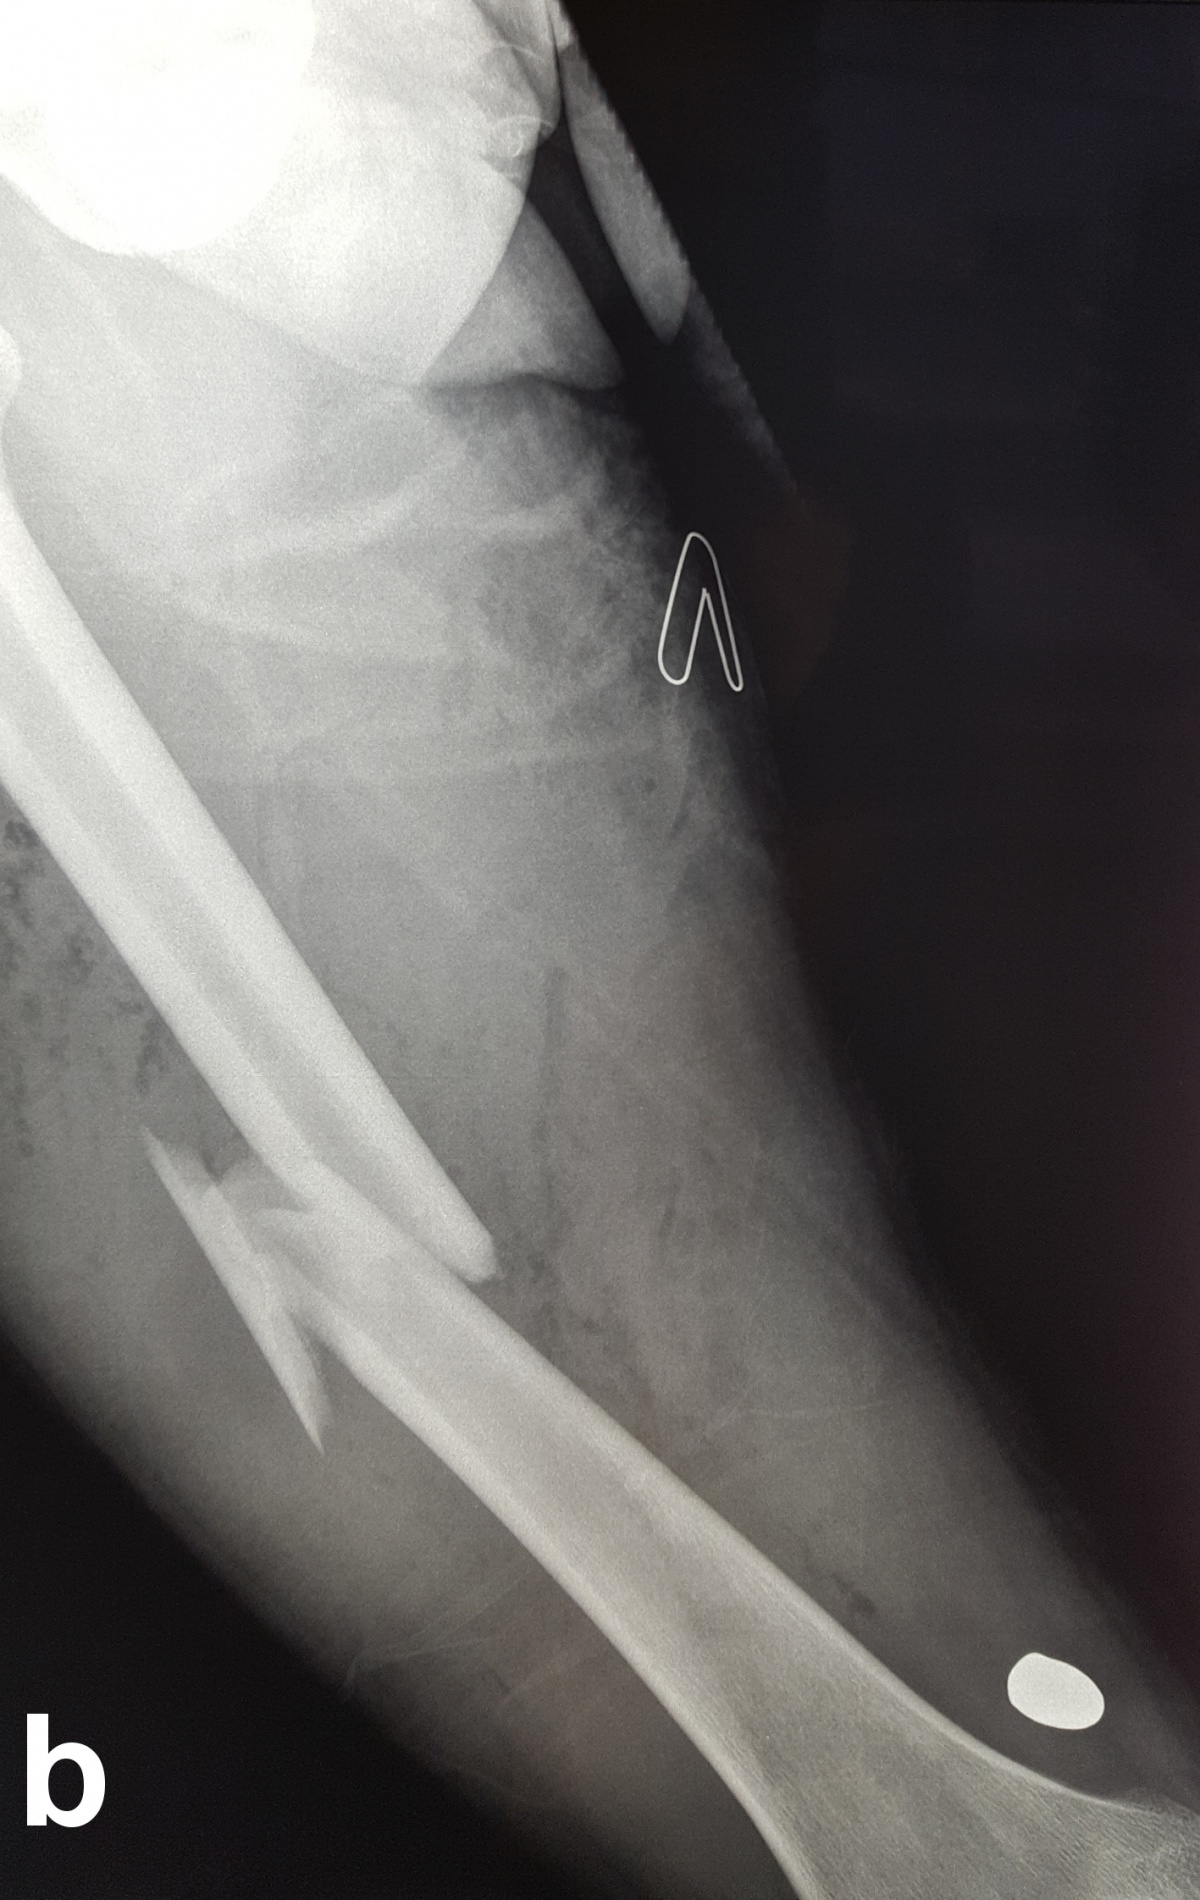

Es zeigt sich das typische Bild einer Schussfraktur nach Niedrigenergieverletzung. a seitlicher Strahlengang,

b a. p. Strahlengang

Beim Auftreffen des Projektils im Rahmen von Niedrigenergieverletzungen auf Knochengewebe entsteht meist eine typische, einfache Fraktur (Abbildung 2). Hochenergieverletzungen des Knochens münden in eine multifragmentäre Situation, bei der ein Großteil der Projektilenergie an den Knochen abgegeben wird. Insbesondere lange Röhrenknochen können, da sie wie eine starre, spröde flüssigkeitsgefüllte Röhre agieren, durch Projektile mit hoher Energie explosionsartig zerstört werden (Abbildung. 3).